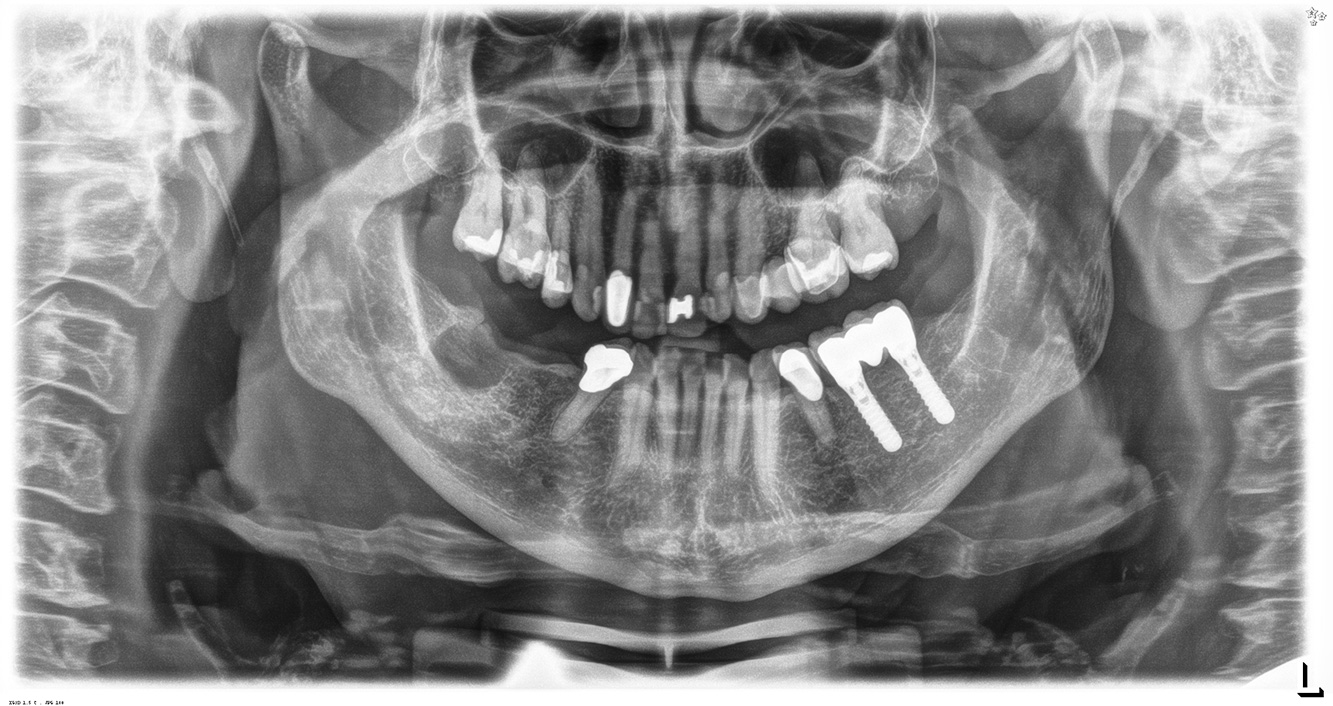

The 68-year-old patient has no general health conditions and is not taking any medication that may be relevant to her oral health, and her lifestyle does not pose any particular risk. The patient has two dental implants (3rd quadrant, for five years) and a previous case of periodontal disease (stage IV, grade B periodontitis) with tooth loss. Currently the periodontal conditions are stable. However, periodontitis significantly increases the biological complications of implantations and there is a risk of implant loss (21). Four recommendations can be determined for the prophylaxis session.

As the patient does not have any particular risk factors with specific dental implications, the requirements determined from her current state of oral health are crucial. Here, it is recommended that a thorough assessment of periodontal condition be carried out once a year. This will ensure that any potential progression of the previous periodontal disease or development of peri-implantitis can be responded to in good time.

Despite the stable conditions, it is also crucial for the instructive/motivational discussion to be conducted with this patient. Particular attention should be paid to teaching the patient how to care for the implants correctly. Here in particular, good at-home maintenance can have a significant impact on the long-term stability of oral and implant health.

In terms of instruments, specific procedures are required for use with implants. In order to preserve the surface of the implant while cleaning it effectively, it is essential to choose suitable powders and instruments such as the targeted use of air polishing devices with special periodontal tips. Which powder is most suitable can be determined according to the needs and risk. For example, in addition to the appropriate degree of abrasion, dietary requirements (including sugar-free, low-salt) may also be taken into account.

Because the patient has implants and a history of periodontal disease, she is at risk of developing peri-implantitis. It is therefore recommended that she attend a recall session every three to four months.